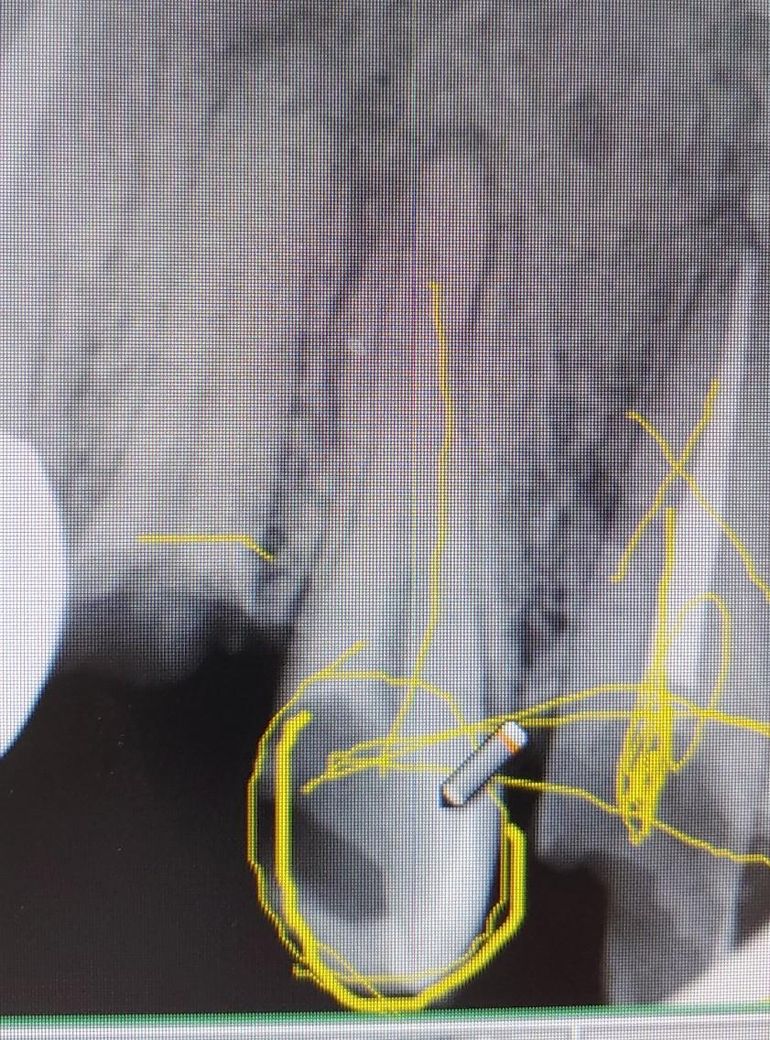

윗쪽 작은어금니인데 신경치료가 필요할까요?

안녕하세요 제가 오른쪽 윗 어금니가 예전부터 충치가 있었는데 충치로 인해 약간 깨져있는 상태인데 신경치료 없이 충치부분만 제거하고 인레이나 크라운으로 씌워서 사용할수 있을까요?

• 1번 째 사진

단순히 인레이나 크라운으로 치료하기엔 충치가 거의 신경과 맞닿아 있어서 힘들어보입니다.

사진으로 봤을 땐 충치가 매우 깊어 보입니다. 사진으로 봤을 때 신경이 많이 나오까지. 충치가 진행되어 있는 것으로 보아 신경 치료가 필요할 것으로 생각됩니다

엑스레이 상으로 치아가 많이 깨지신거 같습니다 저정도면 신경치료후에 기둥도 세우셔야될것같습니다.